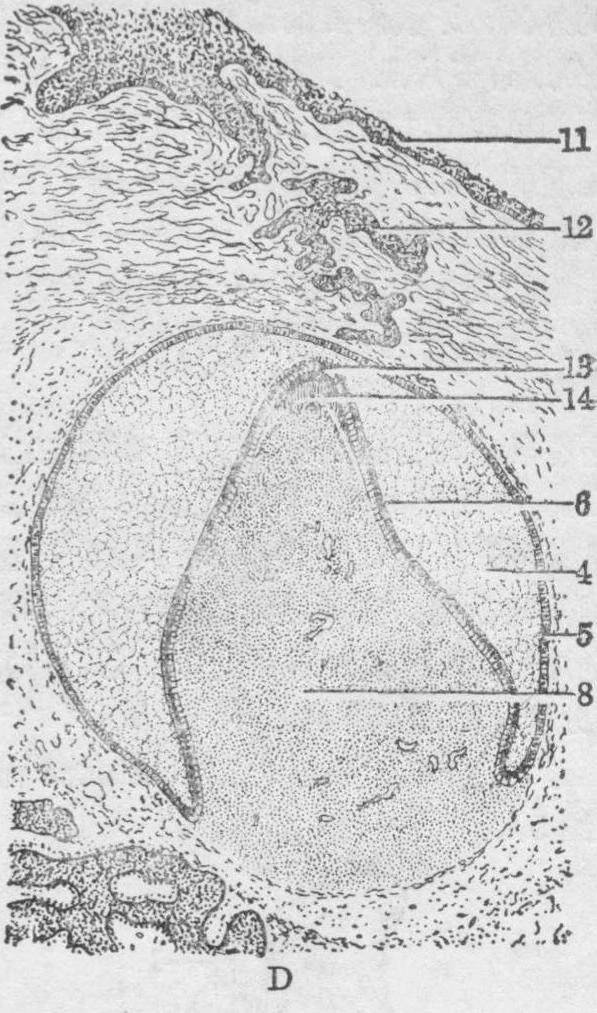

图2 原始口腔的分隔(第6~10周)

A、B. 61/2周 外侧腭突呈垂直方向生长 C.71/2周外侧腭突转向水平方向生长 D.第10周

1.鼻中隔 2.原始口腔 3.舌 4.外侧腭突 5.外鼻孔 6.正中腭突 7.鼻中隔软骨 8.上鼻甲 9.鼻腔 10.中鼻甲 11.下鼻甲 12.腭骨 13.口腔